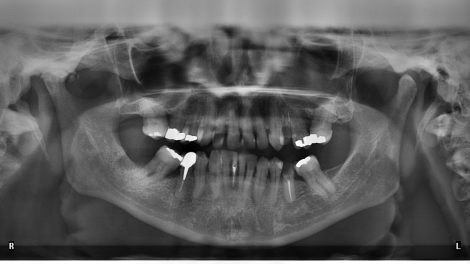

Gli impianti dentali sono usati da decenni per sostituire i denti mancanti e, oggi, si eseguono protesi fisse che possono durare tutta la vita, se ne abbiamo cura. La...

Sempre più spesso ci capita di avere a che fare con Pazienti che, sedotti dal risparmio e dalle lusinghe dei dentisti dell’Est, si rechino in quei paesi solo per farsi...